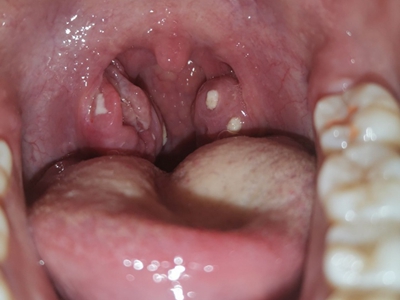

化脓性扁桃体炎单侧扁桃体上有两个黄白色异物图

化脓性扁桃体炎一侧的扁桃体上有黄白色物质,大小不等,形状不规则,镶嵌在增生肿大的扁桃体黏膜上,还可能伴有发热、恶寒、四肢疼痛等症状。